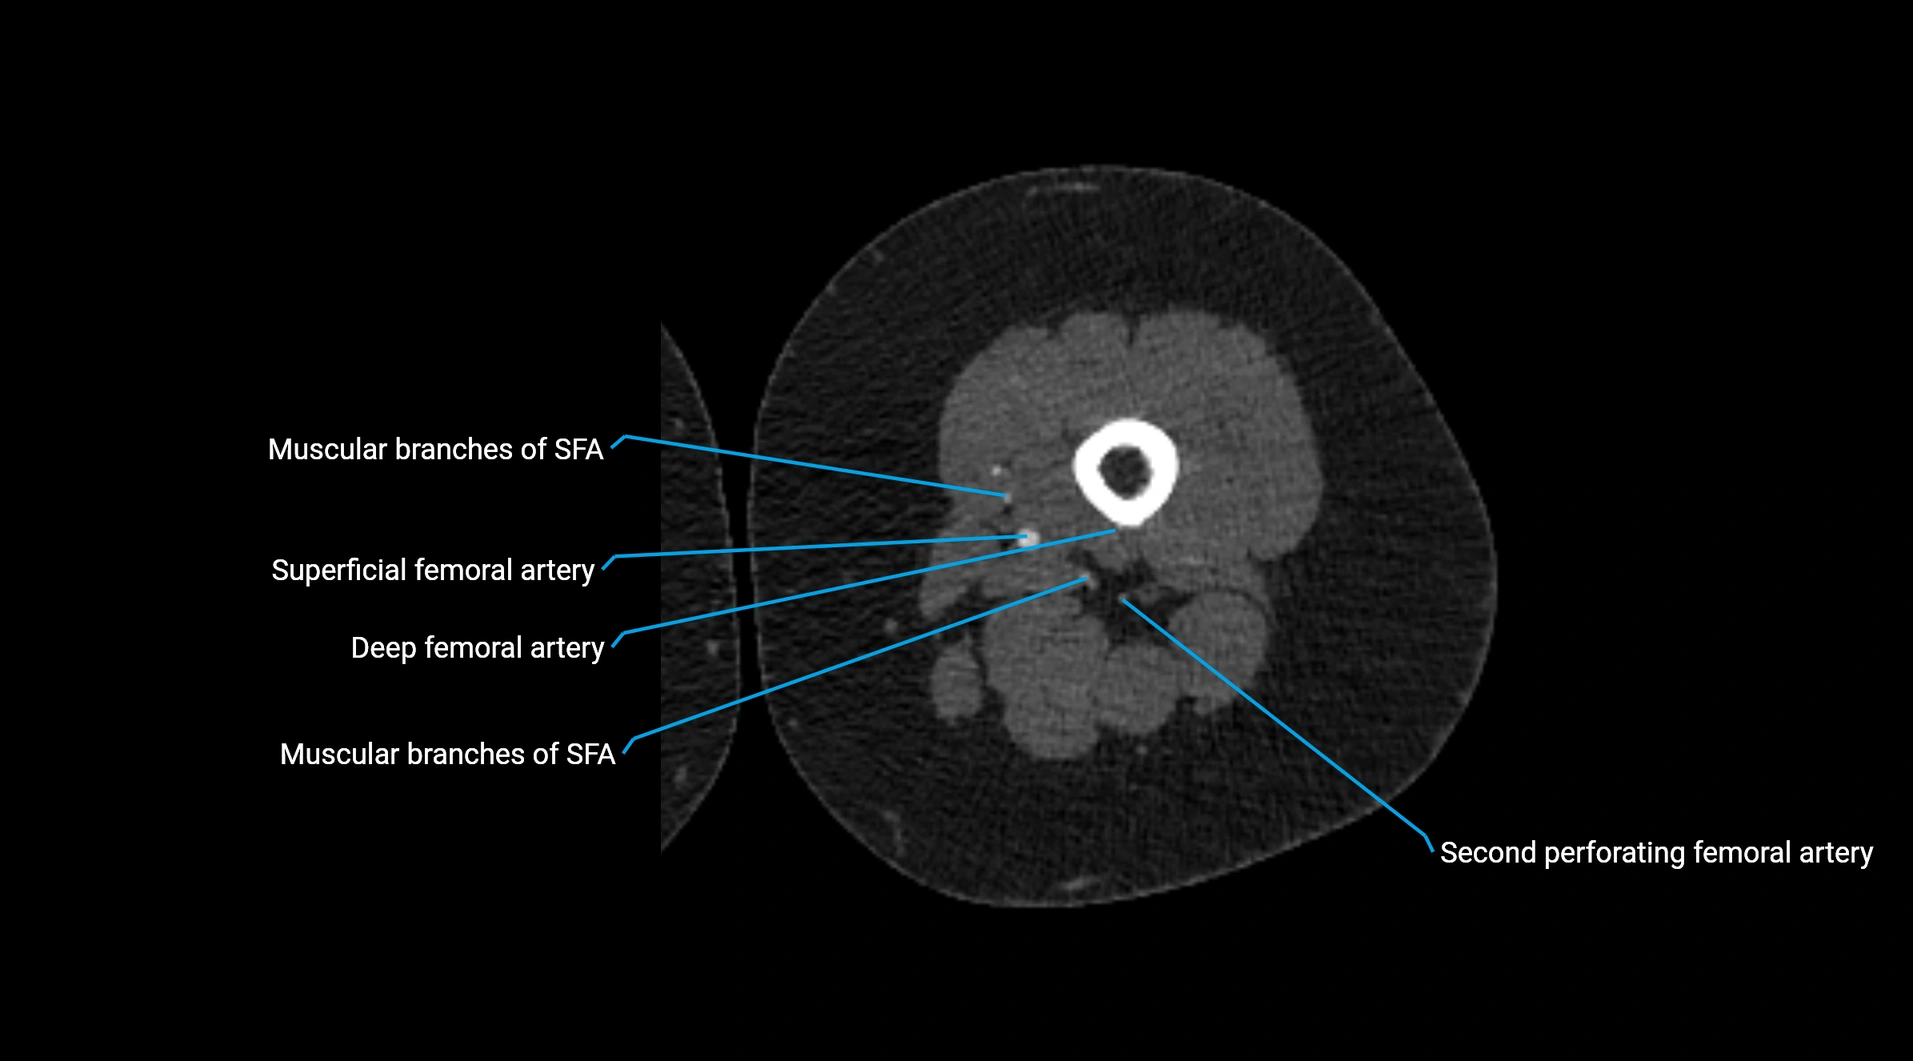

CT images

image